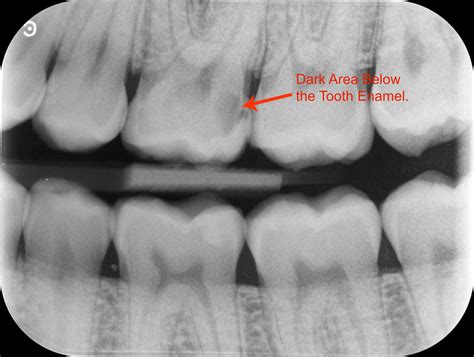

Visual aids, such as teeth with cavities pictures, can be invaluable in understanding the appearance of cavities. These images often show various stages of tooth decay, from early enamel erosion to advanced decay that has reached the pulp of the tooth. By examining these pictures, you can better recognize the signs of cavities in your own teeth.

Here are some key points to look for in teeth with cavities pictures:

• Early Stage Cavities: Small, white spots or discoloration on the tooth surface.

• Moderate Stage Cavities: Visible pits or holes in the enamel, often accompanied by brown or black staining.

• Advanced Stage Cavities: Large cavities that may expose the dentin or pulp, causing significant pain and sensitivity.

• Take X-rays to detect cavities that may not be visible to the naked eye.